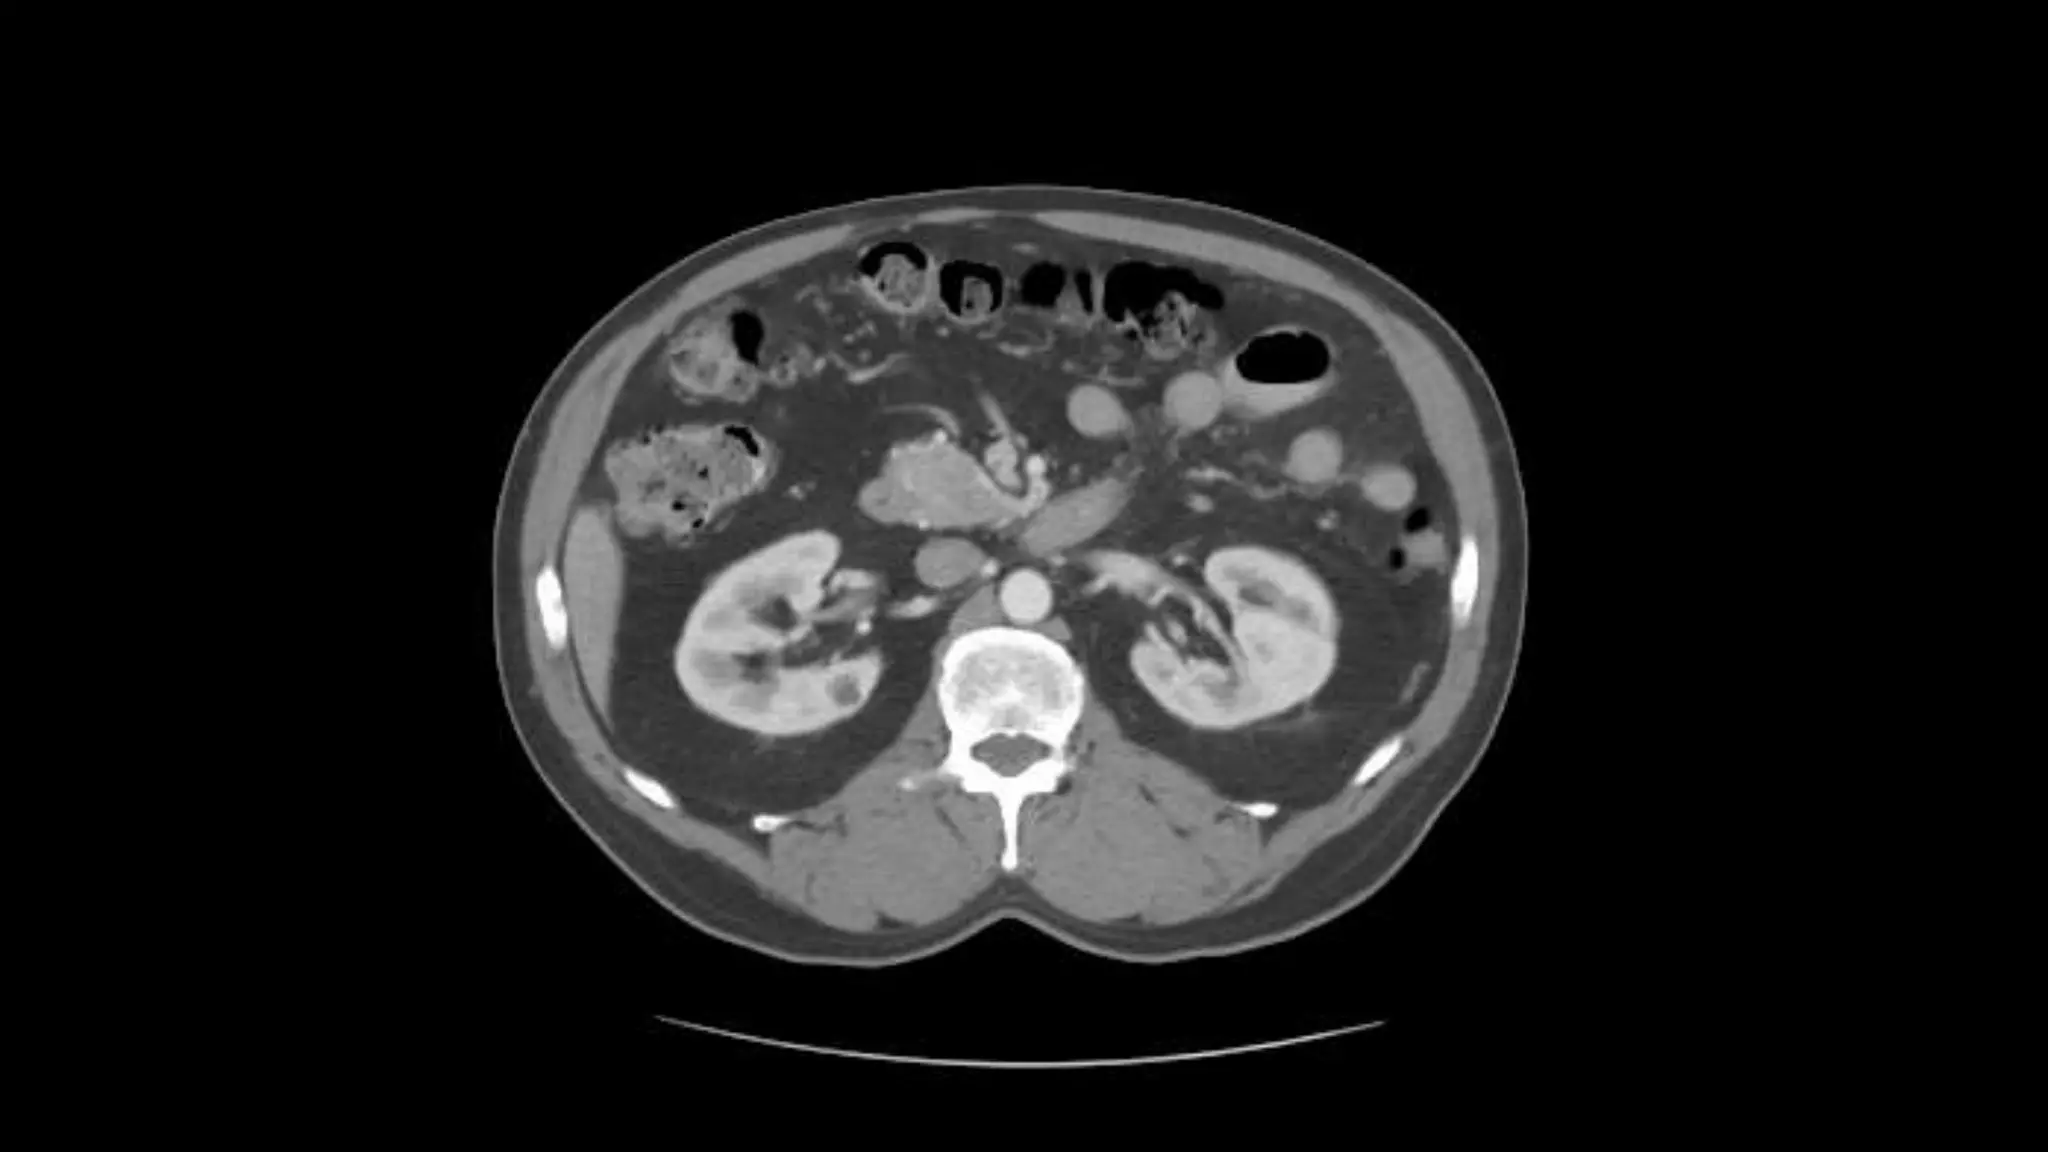

Transverse Colon Small Bowell

Note inferior mesenteric artery emerging from aorta

Inferior mesenteric vein extends cephalad to join smv.

Aorta bifurcates into common illiac arteries

Appendix is noted coiling in Rt. Lower quadrant

Note air in lumen on adjacent scans

Psoas

muscles

Note inferior mesentericartery emerging from aorta Inferior mesenteric vein extends cephalad to join smv.

Aorta bifurcates intocommon illiac arteries Appendix is noted coiling in Rt. Lower quadrant Note air in lumen on adjacent scans Psoas muscles